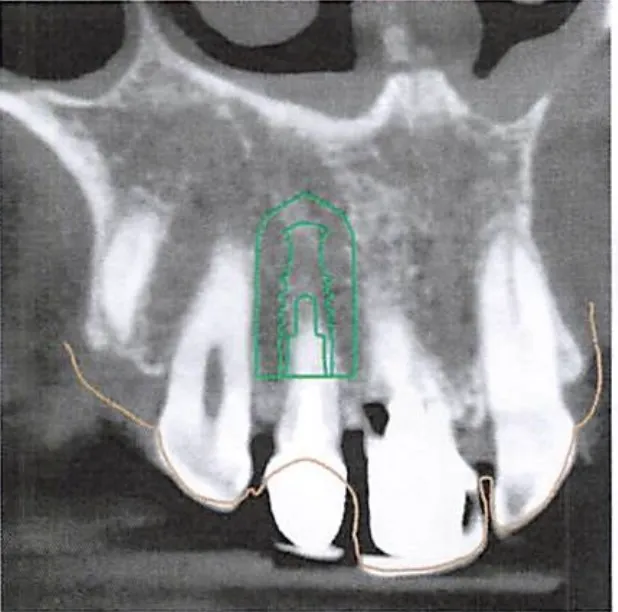

3D Imaging

We map bone density, nerve pathways, and surrounding structures. This is the foundation for everything.

Digital planning

We determine exactly where your tooth needs to sit — for proper function and natural aesthetics.

Foundation assessment

When a tooth has been missing for months or years, bone and gum tissue recede.

We rebuild the foundation first — grafting bone and tissue so the implant can be positioned where it should be, not just where there's room.

Surgical guide

The planned position is translated into a precision guide that directs placement during surgery.

No estimation — the thinking is done beforehand.

If a tooth has been missing for months or years, the jawbone where it sat has likely receded. Bone grafting rebuilds that foundation so the implant can be positioned where it should be — not just where there's room.

It's a separate procedure done before implant placement, and adds to the overall timeline and cost. We assess bone density with 3D imaging during your first consultation, so you'll know upfront whether grafting is needed.